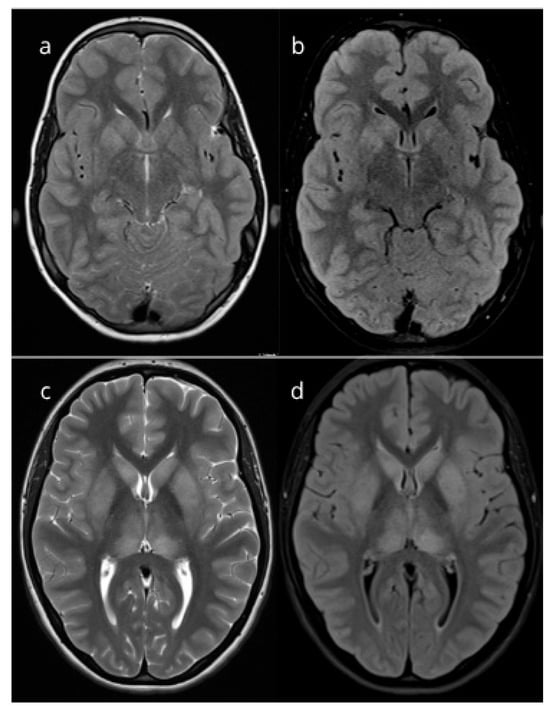

Background: Mycoplasma pneumoniae is a common cause of respiratory tract infections in children, but neurological complications, including encephalitis, are increasingly recognized. Basal ganglia involvement is rare, and a poorly characterized feature of meningoencephalitis, with clinical consequences being inconclusive. Methods: We report two pediatric

Background: Mycoplasma pneumoniae is a common cause of respiratory tract infections in children, but neurological complications, including encephalitis, are increasingly recognized. Basal ganglia involvement is rare, and a poorly characterized feature of meningoencephalitis, with clinical consequences being inconclusive. Methods: We report two pediatric cases of Mycoplasma pneumoniae-related meningoencephalitis with bilateral basal ganglia lesions seen on MRI. A literature review was conducted using PubMed, Scopus, and Web of Science to identify reports of M. pneumoniae-related meningoencephalitis in children, and related MRI findings. Results: Both patients (12-year-old male and 14-year-old female) presented with acute meningoencephalitis syndrome and had marked mononuclear pleocytosis. In both patients M. pneumoniae was confirmed with serological assay from serum sample, while in one patient M. pneumoniae was also confirmed by PCR from pharyngeal swab. Both exhibited bilateral basal ganglia lesions, with complete regression observed during follow-up. Treatment with corticosteroids led to full recovery in both cases. After a literature search, a total of 21 patients had basal ganglia involvement reported. Conclusions: Literature suggests variable MRI findings in pediatric M. pneumoniae encephalitis, with basal ganglia involvement being uncommon and rarely reported, especially among older children. While diagnostic challenges related to extrapulmonary manifestations of the infection persist, basal ganglia involvement could aid in diagnosis, especially in older children presenting with meningoencephalitis along with pronounced pleocytosis when respiratory symptoms are absent or mild.

Figure 1